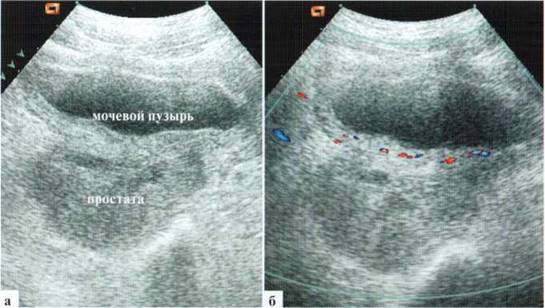

2.11. Простатит

Простатит сам по себе не вызывает клинического синдрома отечной и гиперемированной мошонки, но воспалительный характер заболевания заставляет рассмотреть его в этом разделе. Встречается заболевание в детском возрасте очень редко и почти исключительно у подростков, когда этиология заболевания включает в себя совокупность инфекционного процесса и застойных явлений. Клинические проявления неспецифические, схожи с проявлениями цистита, при этом изменения в анализах мочи сомнительные. Кроме того, необходимо учитывать, что подростки скрывают свои истинные ощущения и/или значительно дезагравируют проявления заболевания. Возможны явления простатита и у детей младшей возрастной группы с аноректальными пороками развития, ректоуретральными свищами и инфекционно-воспалительными изменениями в зоне пороков. Однако достоверное выделение клинико-эхографических проявлений собственно простатита из всей массы патологических проявлений малореально и ненужно, поскольку лечение основного заболевания будет излечивать и простатит. Эхографически определяется увеличение и неровность контуров железы, диффузно-неравномерное понижение ее эхогенности. Одновременно может отмечаться утолщение стенки мочевого пузыря (рис. 2.11.1).

Рис. 2.11.1. Простатит у подростка 15 лет, трансабдоминальное сканирование; а — исследование в В-режиме; б — цветовое допплеровское исследование (гиперемия стенки мочевого пузыря)